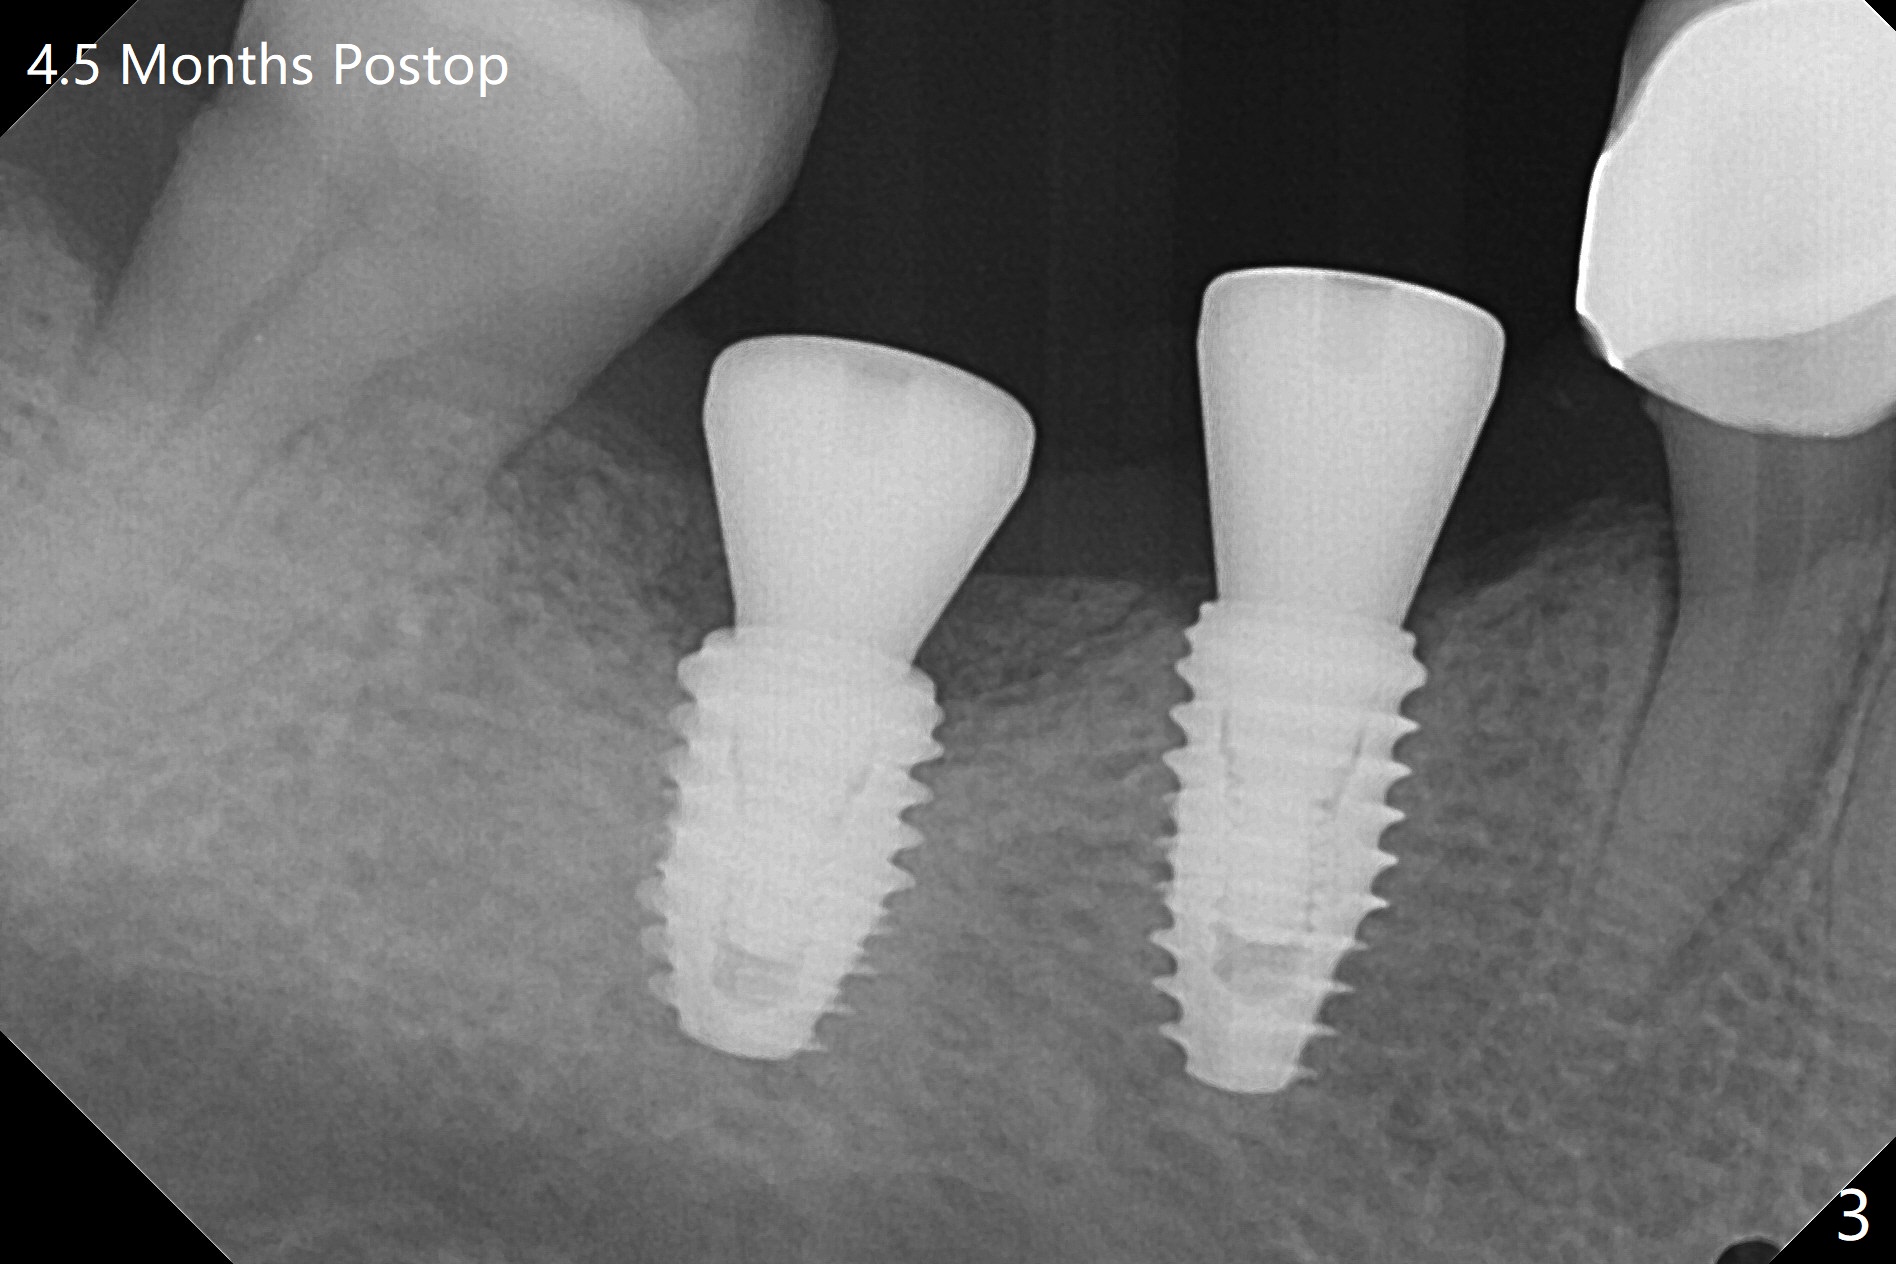

There is no bone loss 4.5 months postop (Fig.3).  With placement of 4.5x4.5(3) and 5.2x4.5(4) mm abutments at #29 and 30, respectively, no limited orthodontic treatment seems to be needed.